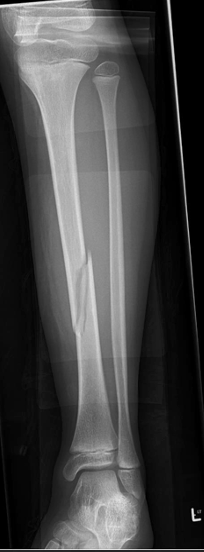

in the shown radiograph

1- what type of fracture

2- site of fracture

A

Oblique fracture of tibial mid shaft